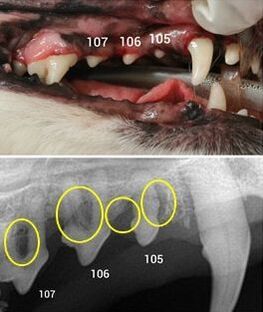

육안으로는 크게 문제가 없는것처럼 보이지만 실제로는 문제가 심각한 증례 사진 서베이 from google image